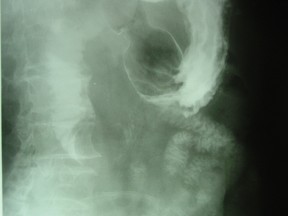

女 ,80岁 ,右上腹疼痛反复发作 6个月,加重 2天 ,曾有胆囊炎及胆结石病史,影像检查如图,应诊断为 ( ) WXJ-04341.jpg WXJ-04342.jpg WXJ-04343.jpg

• A.十二指肠巨大胆结石(胆囊十二指肠瘘)